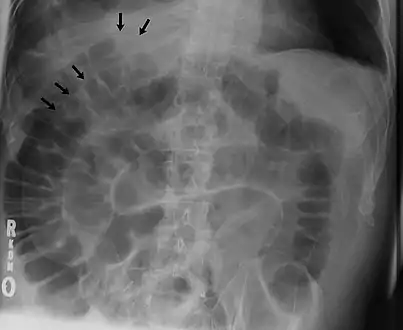

Signs that can be seen on projectional radiography are shown below:

The double wall sign marks the presence of air on both sides of the intestine.[19] However, a false double wall sign can result from two loops of bowel being in contact with one another.[20] The sign is named after Leo George Rigler.[21] It is not the same as Rigler's triad.